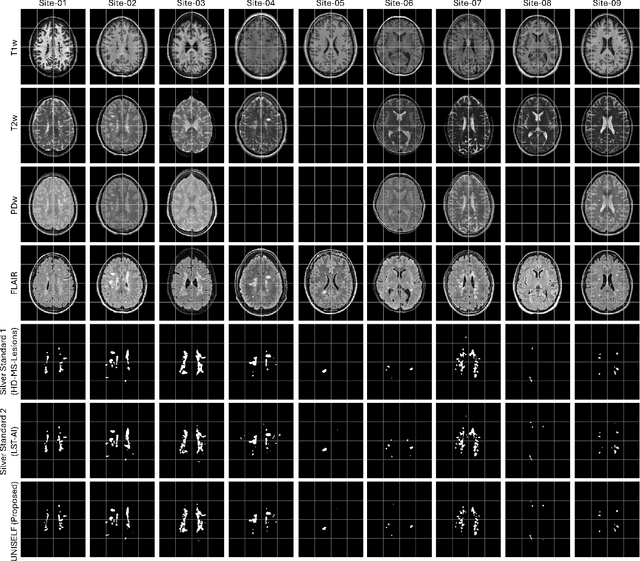

Abstract:Modern deep learning methods have achieved impressive results across tasks from disease classification, estimating continuous biomarkers, to generating realistic medical images. Most of these approaches are trained to model conditional distributions defined by a specific predictive direction with a specific set of input variables. We introduce MetaVoxel, a generative joint diffusion modeling framework that models the joint distribution over imaging data and clinical metadata by learning a single diffusion process spanning all variables. By capturing the joint distribution, MetaVoxel unifies tasks that traditionally require separate conditional models and supports flexible zero-shot inference using arbitrary subsets of inputs without task-specific retraining. Using more than 10,000 T1-weighted MRI scans paired with clinical metadata from nine datasets, we show that a single MetaVoxel model can perform image generation, age estimation, and sex prediction, achieving performance comparable to established task-specific baselines. Additional experiments highlight its capabilities for flexible inference. Together, these findings demonstrate that joint multimodal diffusion offers a promising direction for unifying medical AI models and enabling broader clinical applicability.